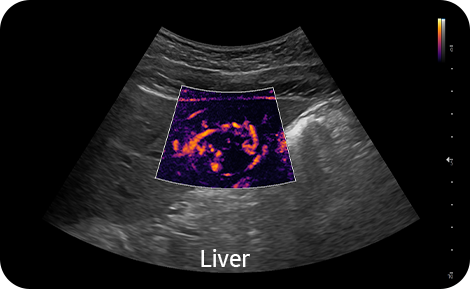

Vizualizace pomalého toku v mikrovaskulárních strukturách |

MV-Flow™ nabízí pokročilé barevné zobrazení pro vizualizaci pomalého průtoku v mikrovaskulárních strukturách. Vysoká snímková frekvence a pokročilé filtrování umožňují MV-Flow™ poskytnout detailní pohled na průtok krve, ve vztahu k okolní tkáni nebo patologii, se zvýšeným prostorovým rozlišením.